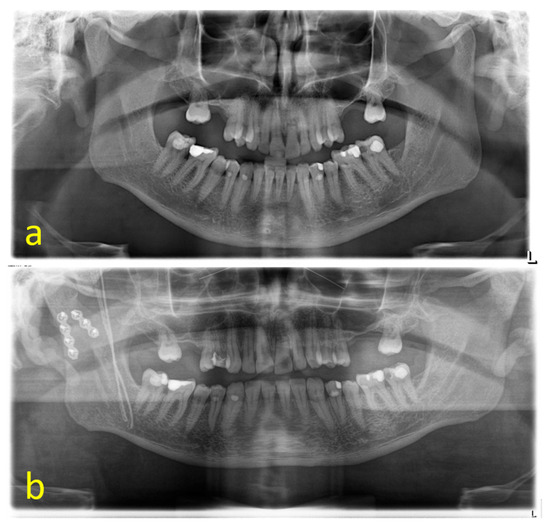

The cases could be subdivided in 62 unilateral and 53 bilateral fractures. A total of 107 of the 115 fractures were treated by ORIF (93.0%); 8 underwent conservative therapy (7.0%). Conservative treatment by intermaxillary fixation was carried out for a mean of 23.57 ± 10.37 days. According to the Spiessl and Schroll classification, the dominant type of fracture was type II (n = 61; 53.0%) (Figure 1a) followed by type III (n = 22; 19.1%), type I and V (n = 15; 13.0% each), and type IV (n = 2; 1.7%). Type I was present in 62.5% of conservatively treated fractures (n = 5), whereas 97.0% of the displaced or dislocated fractures underwent ORIF (n = 97) (Figure 1b). Type IV and V fractures exclusively received open treatment. This distribution was statistically significant (p < 0.001). A total of 15 fractures were classified as comminuted fractures by reference to preoperative 3D imaging (Figure 2a–c). A retromandibular transparotid approach was chosen in 93.5% of the open-treated cases (n = 100) (Figure 3a–f).

Figure 2. Comminuted type II fracture: CT-scan (a); preoperative panoramic x-ray (b); postoperative panoramic x-ray (c).